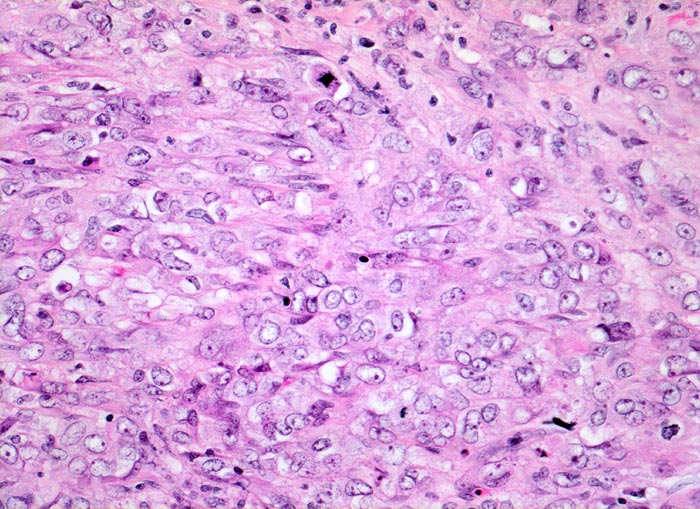

Morphologische Merkmale:

• Solider Tumor mit fokalen Entzündungsinfiltraten.

• Polymorphe Tumorzellen mit unscharfen Zellgrenzen und bläschenförmigen (=vesikulären) Kernen.

• Zahlreiche Mitosen.

• Ureter mit verdickten Kapillaren (Kapillarosklerose).